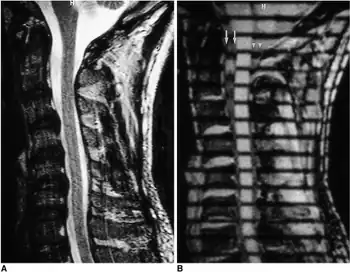

Diagnosis

In terms of the diagnosis of Cervical spinal stenosis we find the following is done:[5]

- Computed tomography (CT) (scan of the spine)

- MRI (spine)